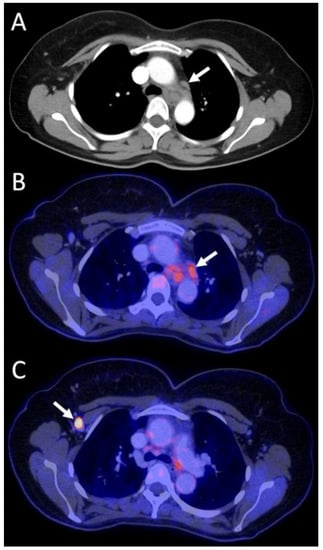

3.4.1. Primary Staging Patients (n = 15/52)

| Group A Staging (n = 15 scans in 15 patients) | Stage I: n = 3 Stage II: n = 6 Stage III: n = 5 Stage IV: n = 1 | surgery + systemic | surgery + systemic | P | C | downstaging, IV → I | yes, invasive | 1 | Major (n = 6) | better customized therapy, major psychological benefit of downstaging, avoidance of invasive tests |

| downstaging, IV → IIa | 1 | |||||||||

| surgery + systemic + RTX | surgery + systemic + RTX | P | C | downstaging, IV → IIb | no | 2 | better customized therapy, major psychological benefit of downstaging | |||

| systemic | systemic | P | C | downstaging, IV → IIIa | yes, invasive | 1 | better customized therapy, major psychological benefit of downstaging, avoidance of invasive tests | |||

| systemic + RTX | systemic + RTX | P | C | downstaging, IV → I | yes, invasive | 1 | better customized therapy, major psychological benefit of downstaging, avoidance of invasive tests | |||

| surgery + systemic + RTX | surgery + systemic + RTX | C | C | no change in stage | yes, not specified | 4 | Minor (n = 4) | avoidance of additional tests | ||

| surgery + systemic + RTX | surgery + systemic + RTX | C | C | no change in stage | no | 3 | No change (n = 5) | |||

| systemic + RTX | systemic + RTX | P | P | no change in stage | no | 2 | ||||